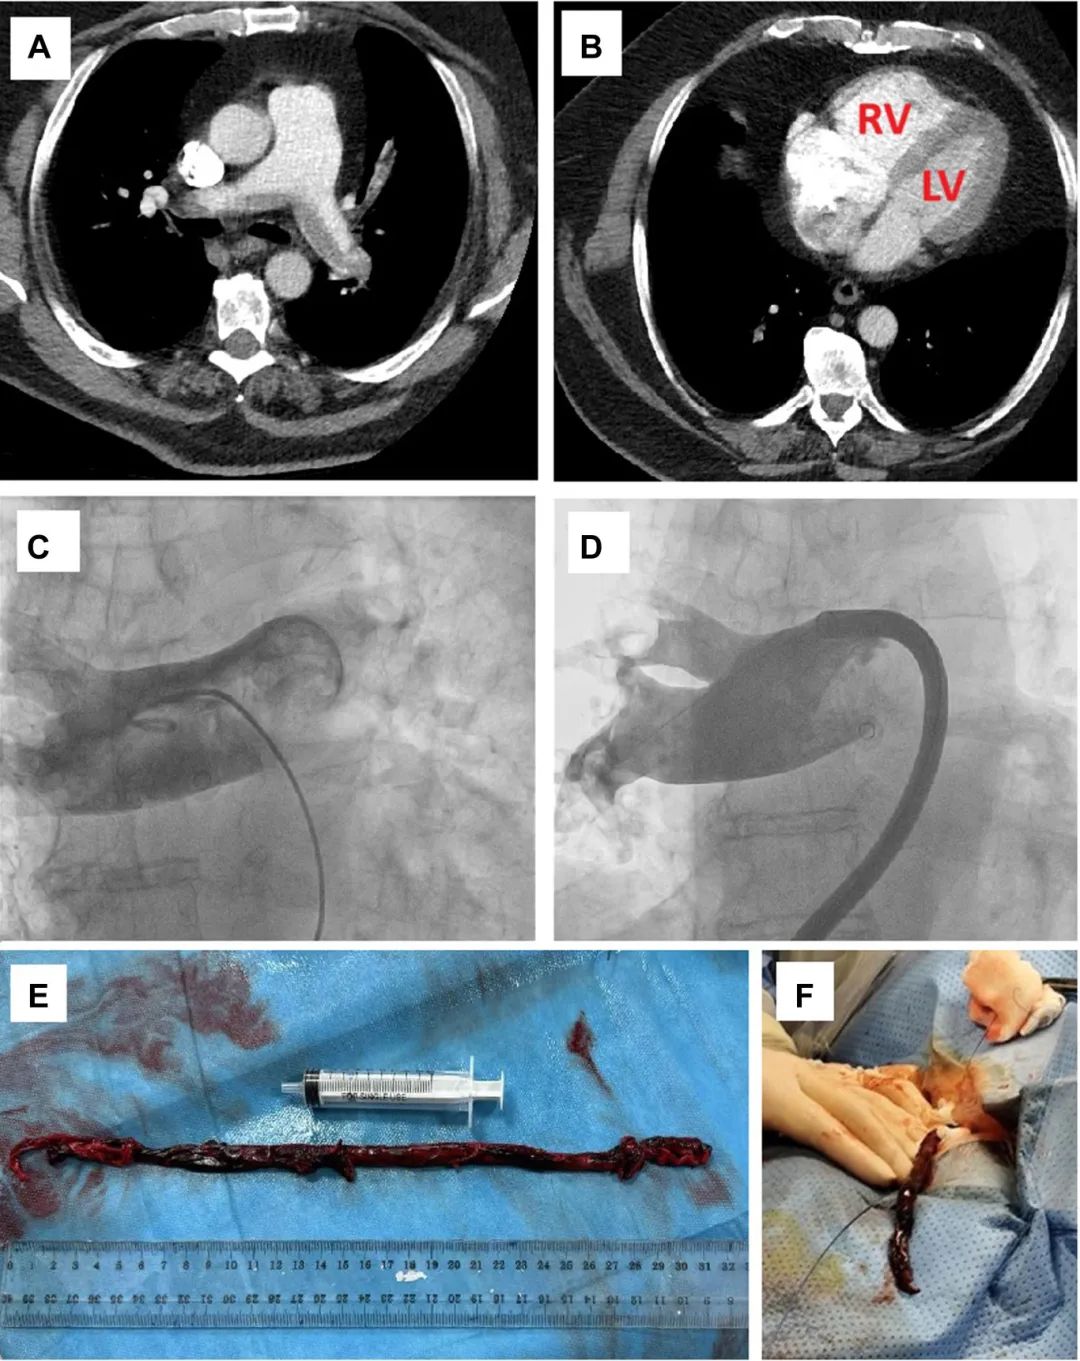

35cm致命栓子惊现肺动脉!看介入治疗如何破解中高危肺栓塞救治困局

病史摘要:43 岁男性,主因进行性加重的呼吸困难和咯血于外院就诊。既往史未提及,现病史为出现上述症状后于外院检查,生命体征提示血压 110/60 mmHg,心率 117 次/分,辅助供氧下氧饱和度 90%,呼吸频率 27 次/分。 诊疗过程:外院超声心动图显示右心室扩张,CT 肺血管造影提示急性肺栓塞累及主肺动脉及其分叉处,高敏心肌肌钙蛋白 I 升高,被归类为中高风险,初用低分子肝素治疗